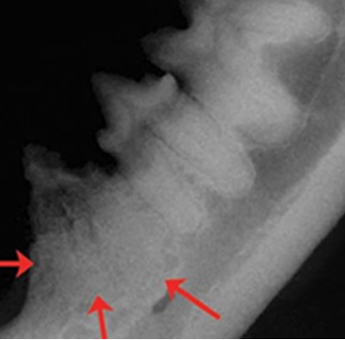

고양이 치아흡수병변이란 파치세포(Odontoclast)에 의하여 치아 뿌리의 표면이 파괴되는 것으로 잇몸 위쪽 치관이 녹거나 잇몸 안쪽의 치근이 녹아 주변 치조골에 흡수되는 질환을 말합니다. 고양이에게 가장 흔한 치과질환 중 하나이며 약 20~30%정도의 고양이에서 발병하고 있는 것으로 알려져있습니다.

병변의 정도에 따라 1~5단계, 형태에 따라 type1~3로 분류하며 고양이의 치아중에서 아래턱 첫 번째 작은 어금니에 가장 흔하게 발생합니다. 진행정도 및 타입에 따라 스케일링, 발치 또는 치관삭제등의 치과치료를 실시하고 약물치료를 병행하기도 합니다.

치아흡수성병변은 주변잇몸염증을 유발하거나 신경통증을 나타낼수 있기 때문에 조기에 발견하는 것이 중요하며 육안상 구분이 어려운경우가 많아 진단을 위해서 치과방사선촬영을 필요로합니다.

치아흡수병변 TYPE 및 예시